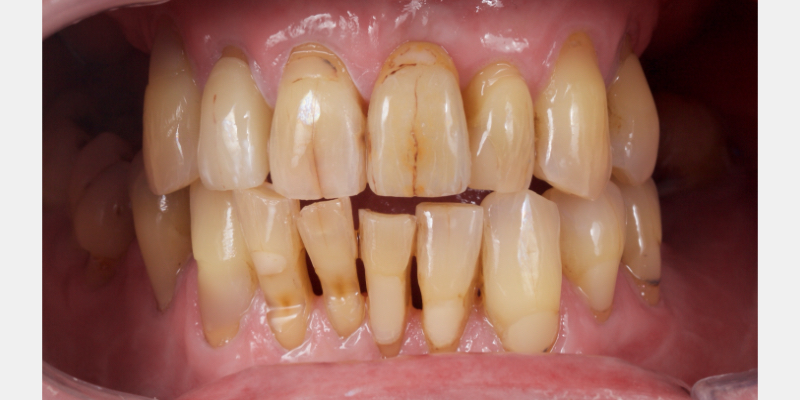

Here’s Elizabeth’s case. She had a periodontal lesion affecting the upper right central incisor (Fig. 13).

The tooth was extracted and a provisional nonprecious adhesive bridge with composite pontic was placed (Figs. 14-16).

The Rochette-type wing was placed on the lateral incisor abutment (Fig. 17). Grafting procedures were carried out before definitive restoration with a lithium disilicate adhesive bridge.